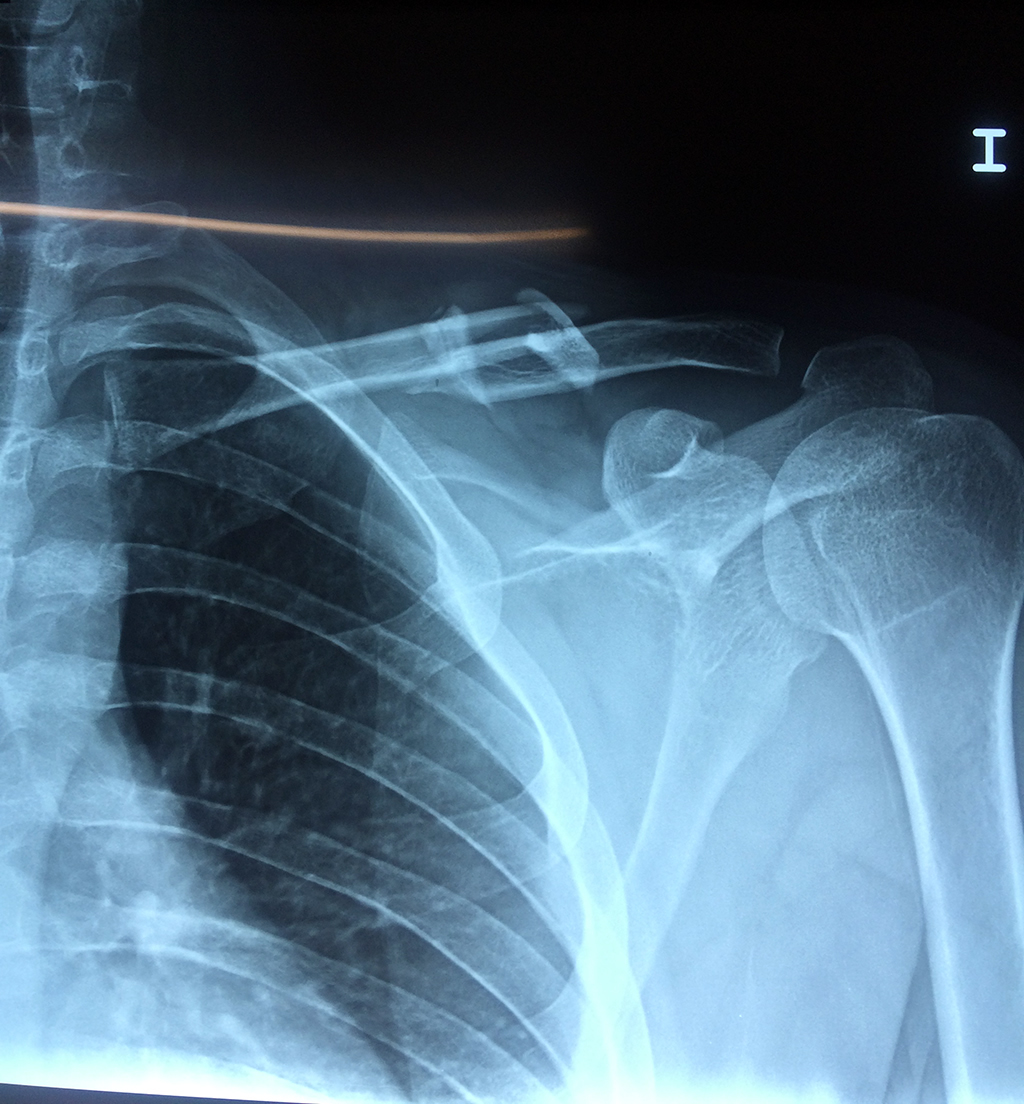

Cirugías de Codos - Clavícula

La clavícula es un hueso largo, con forma de "S" itálica, situado en la parte anterosuperior del tórax. Junto con la escápula forman la cintura escapular. Se puede palpar por toda su longitud y se extiende del esternón al acromion de la escápula, siguiendo una dirección oblicua lateral y posterior.